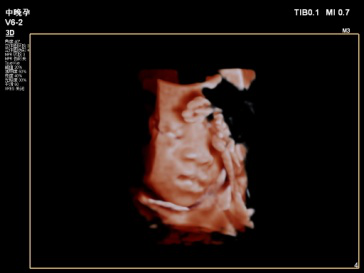

2019年县中医院功能科特引进飞利浦EPIQ5全身高档彩色多普勒超声,配备有心脏、腹部、浅表、腔内及三维容积等5把探头。其专有的purewave纯净波单晶技术,可提高在难以成像的患者身体中的穿透力,使成像更快捷、更清晰;飞利浦EPIQ5在孕期检查中也独具优势,通过图像的切割、旋转及高平面图像的分析,能直观、立体显示胎儿在母体子宫内的立体形态、表面特征、空间位置关系,尤其胎儿面部的三维成像,清晰、直观,准爸爸、准妈妈可以通过屏幕亲眼目睹胎儿的眼睛、嘴巴、鼻子和脸颊,甚至可以看到宝宝在妈妈肚子里运动、呼吸、吞咽、打哈欠、伸舌头等生理活动,非常直观。

每个孕妈妈都希望生个健康的宝宝,因此一定不要忘记这项重要的超声检查哦,不然错过时间可没有办法弥补了。我科室现已正式开展三维彩超,看这些可爱的宝宝!